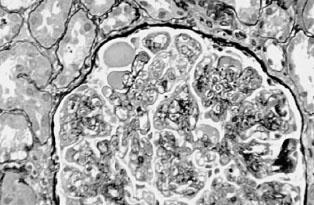

光镜下,FSGS特征性改变是受累的肾小球(<50%)内出现散在节段性分布的毛细血管袢(<50%毛细血管袢)塌陷闭塞,代之以无细胞结构的基质样物质及透明样物质增生,而未累及的节段光镜下相对正常(图2—6)。以皮质近髓部位的肾单位常见。毛细血管壁内可见泡沫细胞,脏层上皮细胞肥大,毛细血管袢与Bowman囊粘连。有时可见肾小管萎缩、间质纤维化也呈灶性分布。肾小动脉内膜出现玻璃样物质沉积,小动脉透明变性,无细胞增生反应。肾小球硬化区节段性IgM、C3积聚,其位置相当于血浆蛋白渗出部位,一般认为是非免疫“滞留”的结果。肾小管蛋白染色常阳性,可能是重吸收的蛋白。

图2—6 局灶节段性肾小球硬化(PASM x400)